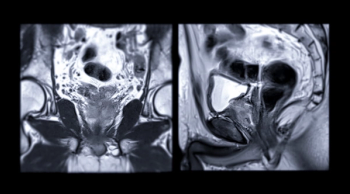

For clinically significant prostate cancer, multiparametric MRI (mpMRI) has a pooled sensitivity rate of 88 percent in biopsy-naïve men, according to a new 16-study meta-analysis.